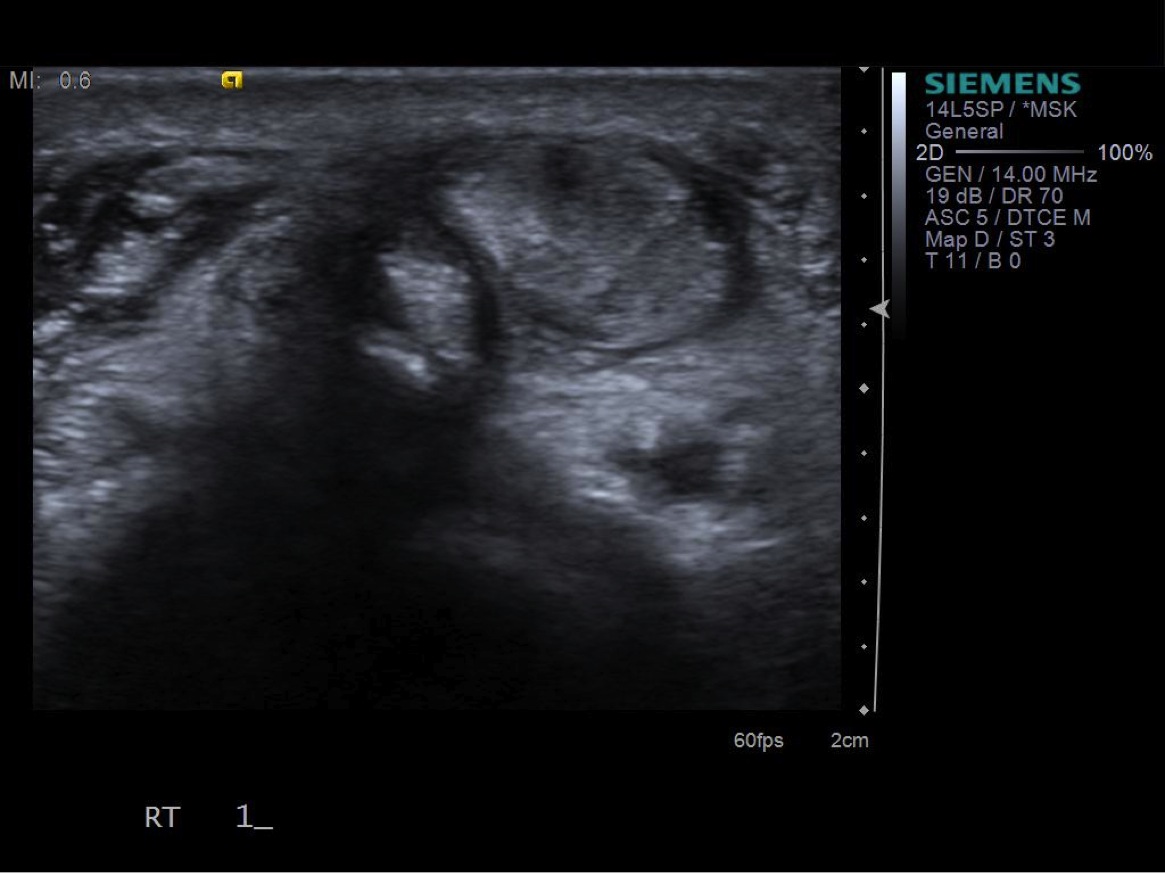

• probe: 14Mhz hockey stick probe

3. Place probe in short axis over first comparment extensor tendons-- Extensor pollicis brevis and abductor pollicis longus. description description

7. Under ultrasound guidance,advance needle into the 1st extensor tendon sheath. In this case the APL and EPB have separate sheaths and require their own injections. Test inject with 1% lidocaine. If no resistance, switch 1% lidocaine for injectable steroid mixture. If there is resistance, reposition needle and test inject again. Inject 1 cc of injectable steroid/anesthetic mixture.